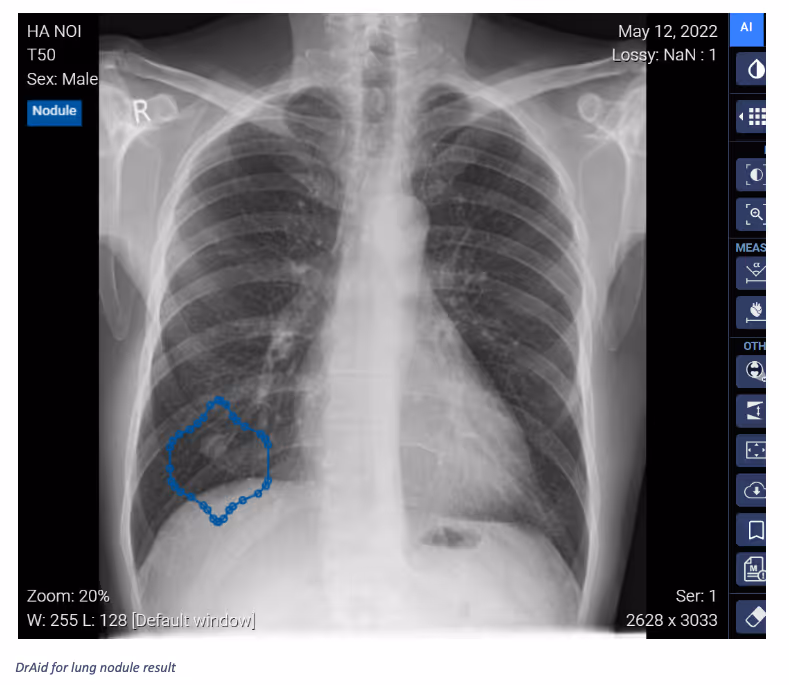

Ferrum Health partners with best-in-class AI providers offering solutions designed to reduce radiology workload and improve patient care.VinBrain Case Study: Detection of Lung Nodule in Easily Confused AreaIntroductionTypically, the structures seen in radiology studies overlap. While some abnormalities may be defined structures—such as a mass, nodule, or tumor—their appearance may not always be so well defined. As such, they may be referred to as lesions, spots, or shadows.Clinical CaseA 55-year-old male joined a chest screening program and had a Chest X-ray image. Through the image, a well-defined solitary pulmonary nodule of soft tissue density is visible in the right lower lobe. Prior examinations confirmed this as a hamartomatous mass.However, after a deep analysis, smaller, symmetrical, ill-defined nodular shadows were detected on both sides between the anterior aspect of the 5th and 6th ribs. Unlike the SPN, these shadows have an ill-defined medial border, while the lateral border is sharp.

ConclusionIt takes a physician time to analyze diagnostic images to distinguish between the appearance of solitary pulmonary nodules and bilateral nipple shadows. The use of DrAid for Lung Nodule takes only 20 seconds to find the exact area of lung nodules without mimicking nipple shadows.Interested in deploying DrAid at your health facility?Contact the Ferrum Health team to learn more.